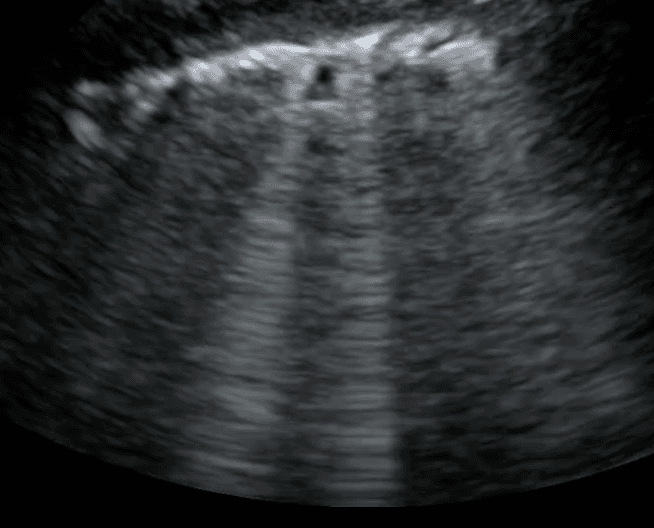

A branch point for the differential diagnosis of B lines includes cardiogenic versus noncardiogenic causes. Integrating lung and cardiac ultrasound can be helpful, as left ventricular dysfunction or valvular heart disease with diffuse, bilateral B lines is highly indicative of cardiogenic pulmonary edema. In these cases, B lines can be monitored daily in order to guide optimal diuretic dosing. In contrast, diffuse, bilateral B lines with a normal heart ultrasound points toward a noncardiogenic cause of pulmonary edema, including ARDS or multifocal pneumonia.